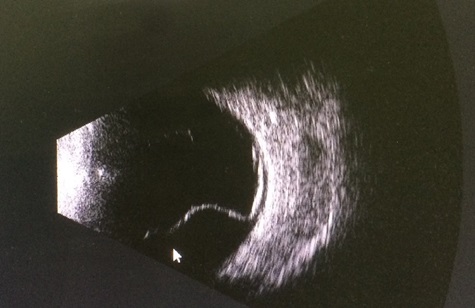

2. Ultrasound scanning in 2-D or 3-D mode. Allows you to define a detachment through the opaque optical medium of the eye or areas inaccessible to the examination… You can determine its height, the contents under it, the relief, the thickness of the shells — this is important.

2.在2-D或3-D模式下进行超声扫描。 允许您定义不透明的眼睛光学介质或检查所无法触及的区域的分离……您可以确定其高度,其下的内容物,浮雕和壳的厚度-这很重要。